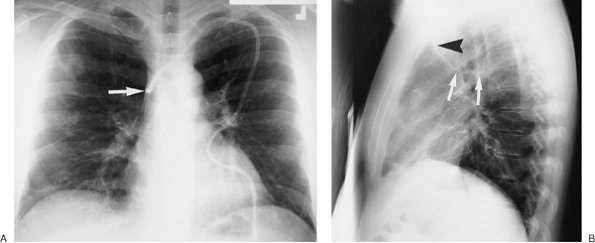

Electrode dislodgment occurs in 3% to 14% of patients (22), generally during the first weeks following insertion. Late displacement is uncommon because of the fibrin sheath that develops between the electrode and the endocardium. Twiddler's syndrome is a rare complication seen in patients with implanted pacemakers or defibrillators; it is a result of the patient either consciously or unconsciously twisting and rotating the implanted device in its pocket, resulting in torsion, dislodgment, and often fracture of the implanted lead (23,24). The diagnosis is confirmed by a chest radiograph, which will reveal a twisted, entangled, and dislodged pacing lead. A small amount of catheter play should be present during systole, but

P.72

none should be present during diastole. If the catheter is short, dislodgment may occur, and the catheter may enter the right atrium, pulmonary artery, SVC, or coronary sinus. If the lead is too long, a bend in the wire may occur, causing lead fracture (Fig. 5-22). A redundant lead may also perforate the myocardium; this complication generally occurs at the time of or within a few days after insertion. The frontal or lateral radiograph will show the catheter tip outside or within 3 mm of the edge of the cardiac silhouette (Fig. 5-23). Perforation can lead to cardiac tamponade or postcardiotomy syndrome. Inflammation and infection can occur within the vein or the generator pocket; the latter occurs in up to 5% of patients (20). Major vein thrombosis and pulmonary embolism are additional complications of pacemaker insertion.